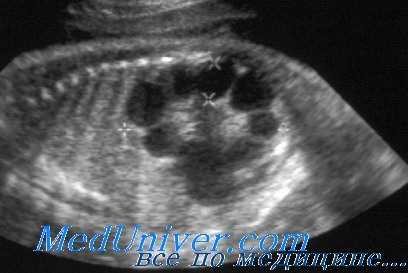

При УЗИ почки резко увеличены, но форма их сохранена. Паренхима имеет повышенную эхогенность, крупнозернистая, с наличием мелких эхонегативных зон («соль с перцем»). На более поздней стадии помимо веретенообразных могут появиться кисты сферической формы. УЗИ печени выявляет повышенную эхогенность, а позднее — хорошо различимые кисты желчных протоков.

УЗИ при поликистозе почек

Диагностика аутосомно-рецессивного поликистоза почек. Пальпируемое двустороннее объемное образования в боковых отделах живота у грудного ребенка с гипоплазией легких, маловодием и артериальной гипертонией в отсутствие поликистоза почек у родителей позволяет диагностировать болезнь. При УЗИ почки обычно резко увеличены и равномерно повышена их эхогенность со стертостью границы между корковым и мозговым веществом. Диагноз подтверждают также клинические и лабораторные признаки фиброза печени, патологические изменения желчных протоков в биоптате печени, наличие поликистоза почек у сиблингов или близкое родство родителей. Аутосомно-рецессивный поликистоз почек следует отличать от увеличения почек при поликистозной дисплазии, гидронефроза, опухоли Вильмса и двустороннем тромбозе почечных вен. В семьях хотя бы с одним больным ребенком возможна пренатальная диагностика с помощью анализа генетического сцепления и использования информативных маркеров.